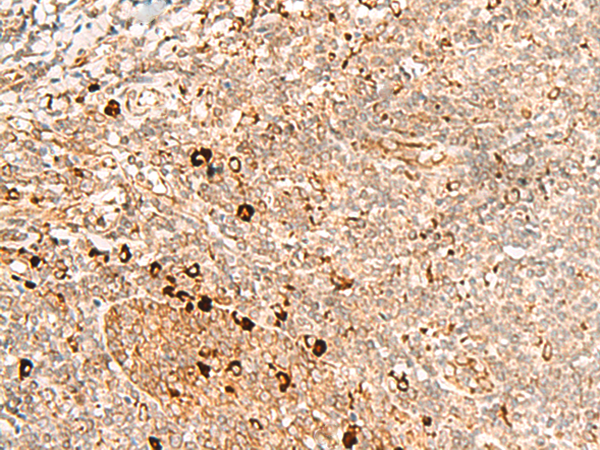

分类: 科研抗体货号: P13549别名: HAD; HCDH; HHF4; HADH1; SCHAD; HADHSC; MSCHAD应用: WB,IHC反应种属: Human, Mouse, Rat